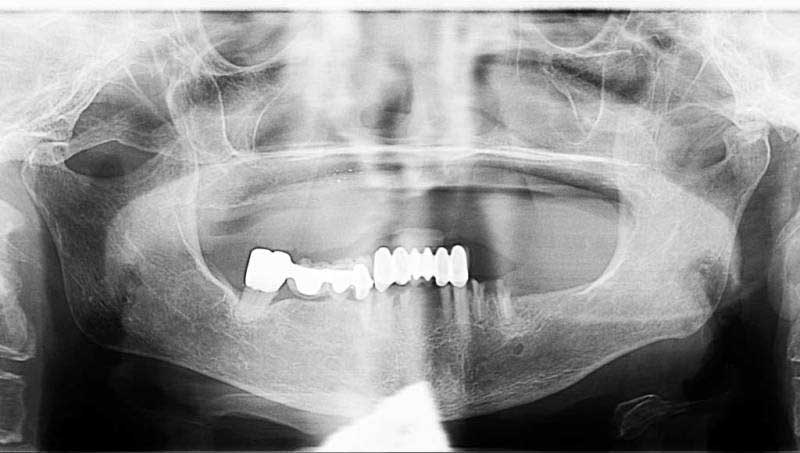

案例1